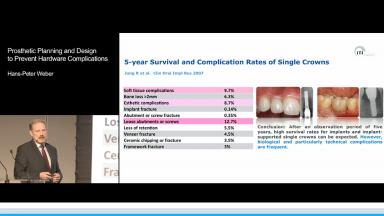

Hardware complications are unavoidable for anyone who is practicing implant dentistry. These complications can be mechanical, such as failure of prefabricated components, or technical, such as failure of a laboratory-fabricated suprastructure or its materials. This lecture presents the importance of keeping the causes of hardware complications in mind while planning the prosthesis design. Also, because complication rates are not the same for every treatment option and material, the clinician should select the abutment and overall materials according to the treatment indications, reserving ceramics for esthetically demanding cases. Finally, this lecture presents the potential limitations of third-party products.

- describe complication rates for removable and fixed prostheses

- discuss clinical recommendations to avoid technical and biological complications